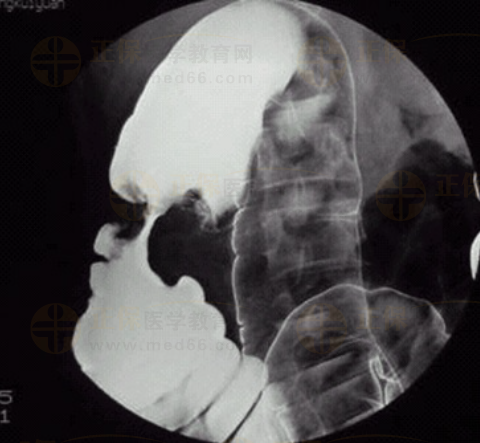

05卷-3.病史:女性,52歲,觸及腹部包塊3周。診斷(本題滿分2.00分)

本題答案:B

【該題針對(duì)“ 造影-結(jié)腸癌 ”知識(shí)點(diǎn)進(jìn)行考核】